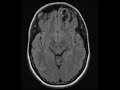

Dysembryoplastic neuroepithelial tumor (DNET)

These images show a wedge-shaped, multi-cystic, expansile, non-enhancing, T2 hyperintense lesion involving the cortex and subcortical white matter of the anterior left frontal lobe. There is minimal surrounding T2 FLAIR hyperintensity which is most prominent deep to the lesion in the adjacent periventricular white matter. No restricted diffusion is present. In this young adult, this imaging appearance is most consistent with a benign entity such as dysembryoplastic neuroepithelial tumor (DNET) or giant tumefactive perivascular spaces. DNETs are usually wedge-shaped bubbly, cystic lesions pointing towards the ventricle, and usually do not demonstrate any enhancement. Most commonly they occur in the mesial temporal lobes, but may be found involving any supratentorial cortex. In patients who present with seizures, surgical resection can be performed and is usually curative.